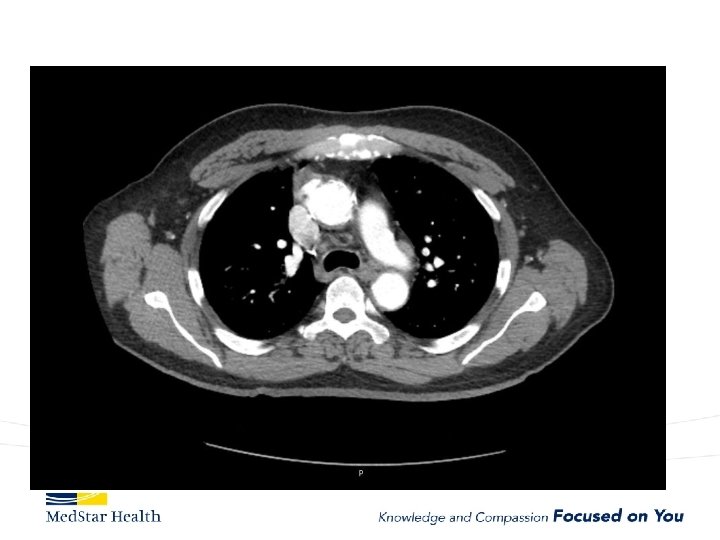

Acute Type B Aortic Dissection • Incidence: 2. 6 -3. 5 per 100, 000 patient-year • Uncomplicated • Complicated – – Malperfusion Rupture Unremitting Pain Uncontrolled HTN

“Uncomplicated” – Type B

Type B Dissection Complicated Uncomplicated Risk TEVAR age, comorbidities Extreme Low Medical Management False Lumen Small, Thrombosed Medical Management Patent/Large(>22 mm), Total Aorta >40 mm TEVAR/adjuncts